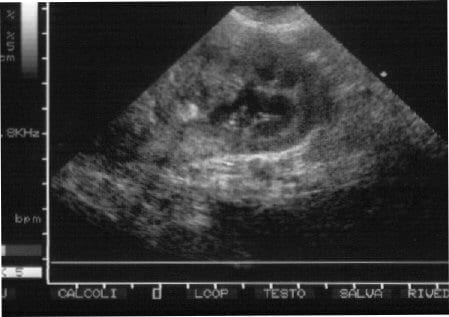

Tumore ovarico di 60 kg: dopo 5 ore, 12 medici tirano fuori la massa e… Chicche di Velvet Tumore ovarico di 60 kg: dopo 5 ore, 12 medici tirano fuori la massa e… Redazione 14 Maggio 2020 Per rimuovere un tumore ovarico di 60 kg, dunque grande quanto un individuo adulto, ci sono voluti...Read More